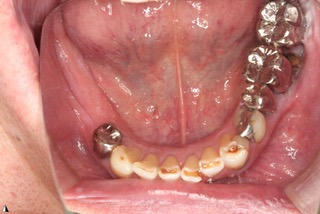

上 before

下 before